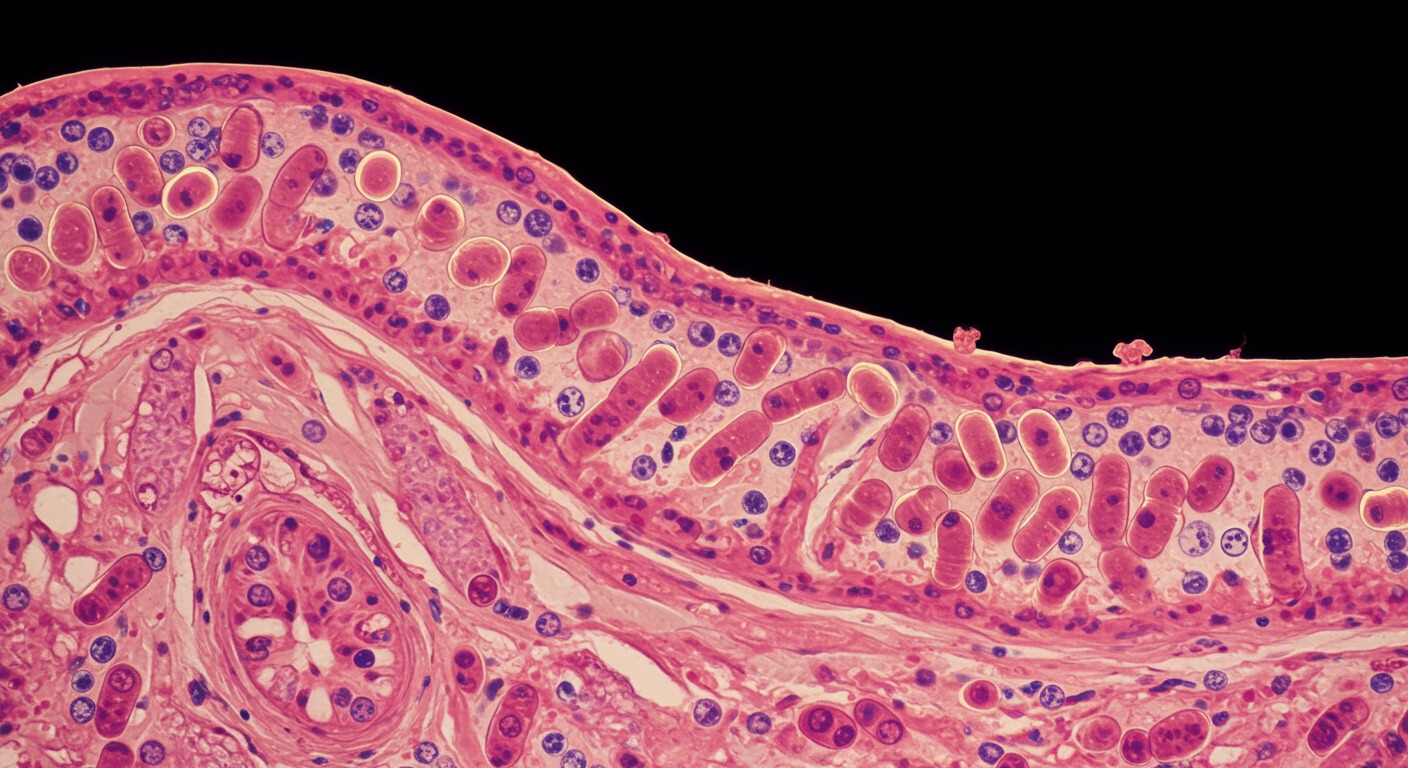

The gastrointestinal system—from mouth to colon—is responsible for digestion, nutrient absorption, immune function, and even neurotransmitter production. As the interface between the external environment and the internal body, gut health has far-reaching effects on overall wellness.